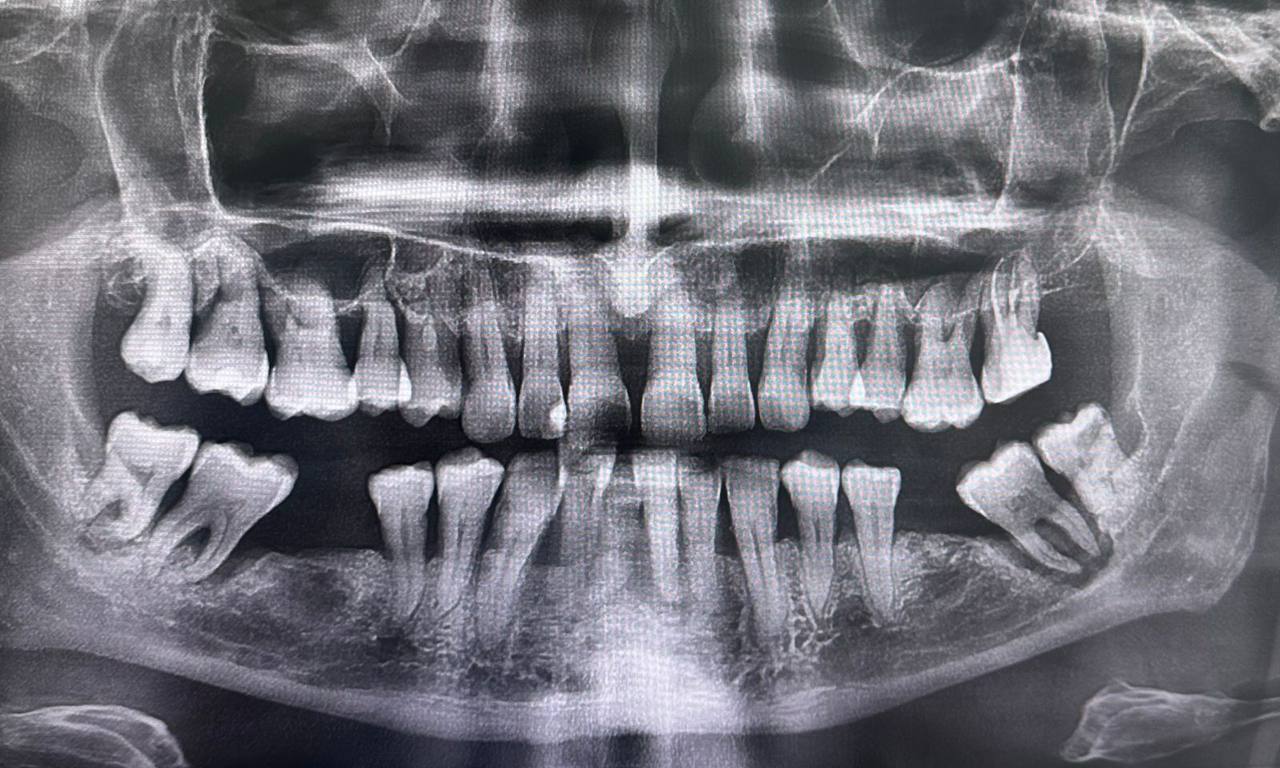

ОПТГ — это рентгенологическая диагностика, которая показывает общее состояние ротовой полости пациента. Врач получает высокоточный 2D-снимок, где видны оба зубных ряда, верхняя и нижняя челюсти, височно-нижнечелюстные суставы, гайморовы пазухи и окружающие костные структуры.

Ортопантомограмма позволяет оценить положение, форму и состояние каждого зуба, а также выявить скрытые патологии, недоступные при визуальном осмотре.

Панорамный рентгеновский снимок челюсти в основном используют для детального осмотра зубов и окружающих их тканей, в том числе ниже линии десны. Вот что он помогает увидеть:

- аномалии развития и положения зубных рядов;

- состояние костной ткани: плотность, структура, наличие воспалений;

- состояние пародонта — тканей, которые удерживают зуб в костной лунке;

- воспаления и другие патологии гайморовых пазух;

- причины нарушения нормальной работы височно-нижнечелюстных суставов и т.д.

Врач получает полное представление о состоянии полости рта пациента, что позволяет разработать оптимальный план лечения.